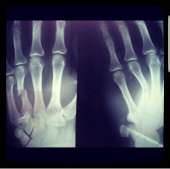

20171001220423.png (1144Кб, 1440x1439)

Screenshot20171[...].jpg (718Кб, 1254x1298)

Такие дела. Прошел пятый год, только сейчас опомнился, надо железку доставать, рука иногда болит, здороваться с крепкими парнямия больно.

Хирург сказал нихуя, перелом с осколками, хуево срастется без него, хотя смотрю на рентген, как-то один хуй криво кость срослась.